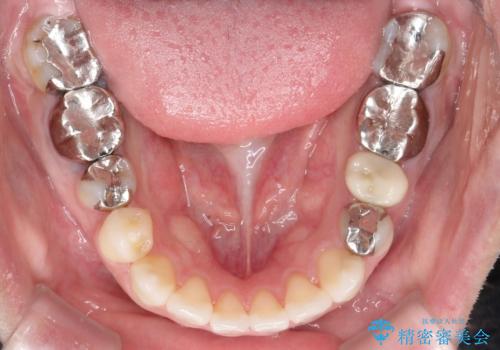

インビザラインで目立たない矯正 ガタガタの歯並びをきれいな歯並びへ

- 10ヶ月

装着時間をしっかり守っていただけたのでスムーズに治療をすすめることができました。